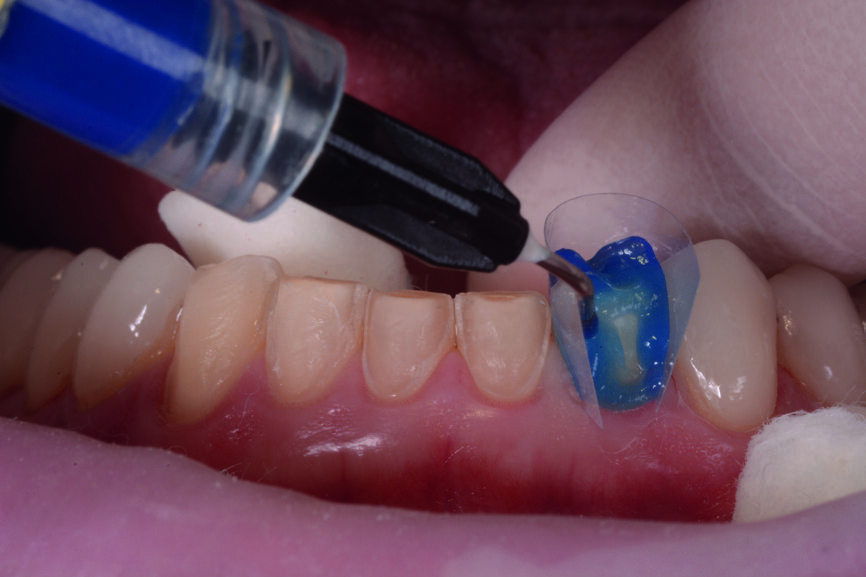

Figs. 11 et 12 : Les couronnes (11–13 et 21–23) et les facettes (14–17, 24–27, 31–37 et 41–47) sont collées sur les dents piliers avec une colle composite photopolymérisable (Futurabond U et Bifix QM).

Les dents piliers, les facettes et les couronnes en céramique sont préparées selon les recommandations du fabricant : la surface de la céramique est sablée avec des particules d’oxyde d’aluminium de 50 μm et mordancée durant 20 secondes à l’acide fluorhydrique à 5 %. Elle est ensuite rincée 20 secondes avant d’être traitée à l’acide phosphorique à 37 % (Total Etch, Ivoclar Vivadent) et à l’alcool à 96 % pour la nettoyer. Pour terminer, elle est conditionnée 20 secondes avec du silane (Monobond Plus, Ivoclar Vivadent).

Les couronnes (#11–13 et 21–23) et les facettes (#14–17, 24–27, 31–37 et 41–47) sont collées sur les dents piliers au moyen d’une colle composite photopolymérisable (Futurabond U et Bifix QM, VOCO). Un dispositif équipé d’une lampe LED à haute puissance (Celalux 3, VOCO) est utilisé pour la photopolymérisation (Figs. 11 et 12).